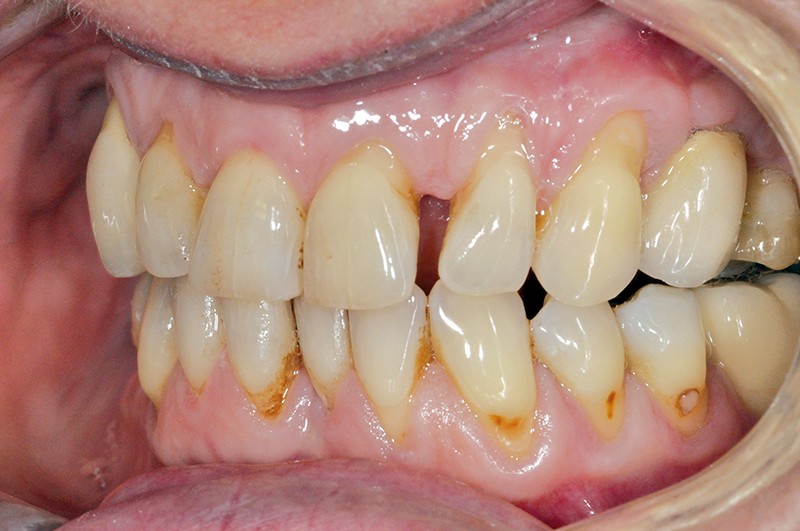

Ainsi, si le brossage « normal » n’altère pas significativement la surface dentaire selon certaines études, un brossage excessif horizontal et appuyé avec un dentifrice fortement chargé en abrasifs, comme le sont les dentifrices dit « blancheur », favorisera sans aucun doute l’ouverture des tubuli et les sensibilités dentinaires. Par ailleurs, l’exposition dentinaire des lésions de collet non carieuses non traitées associées à une hygiène imparfaite favorisera le développement carieux sur ces zones exposées (voir photo). Face à des lésions cervicales non carieuses symptomatiques ou non, le chirurgien-dentiste doit tâcher d’en comprendre les principaux facteurs étiologiques et adopter une thérapeutique adaptée afin d’enrayer la cascade des événements pathogéniques qui aggraveront inévitablement la situation avec le temps. Mais le traitement de ces lésions révèle encore bien d’autres difficultés…